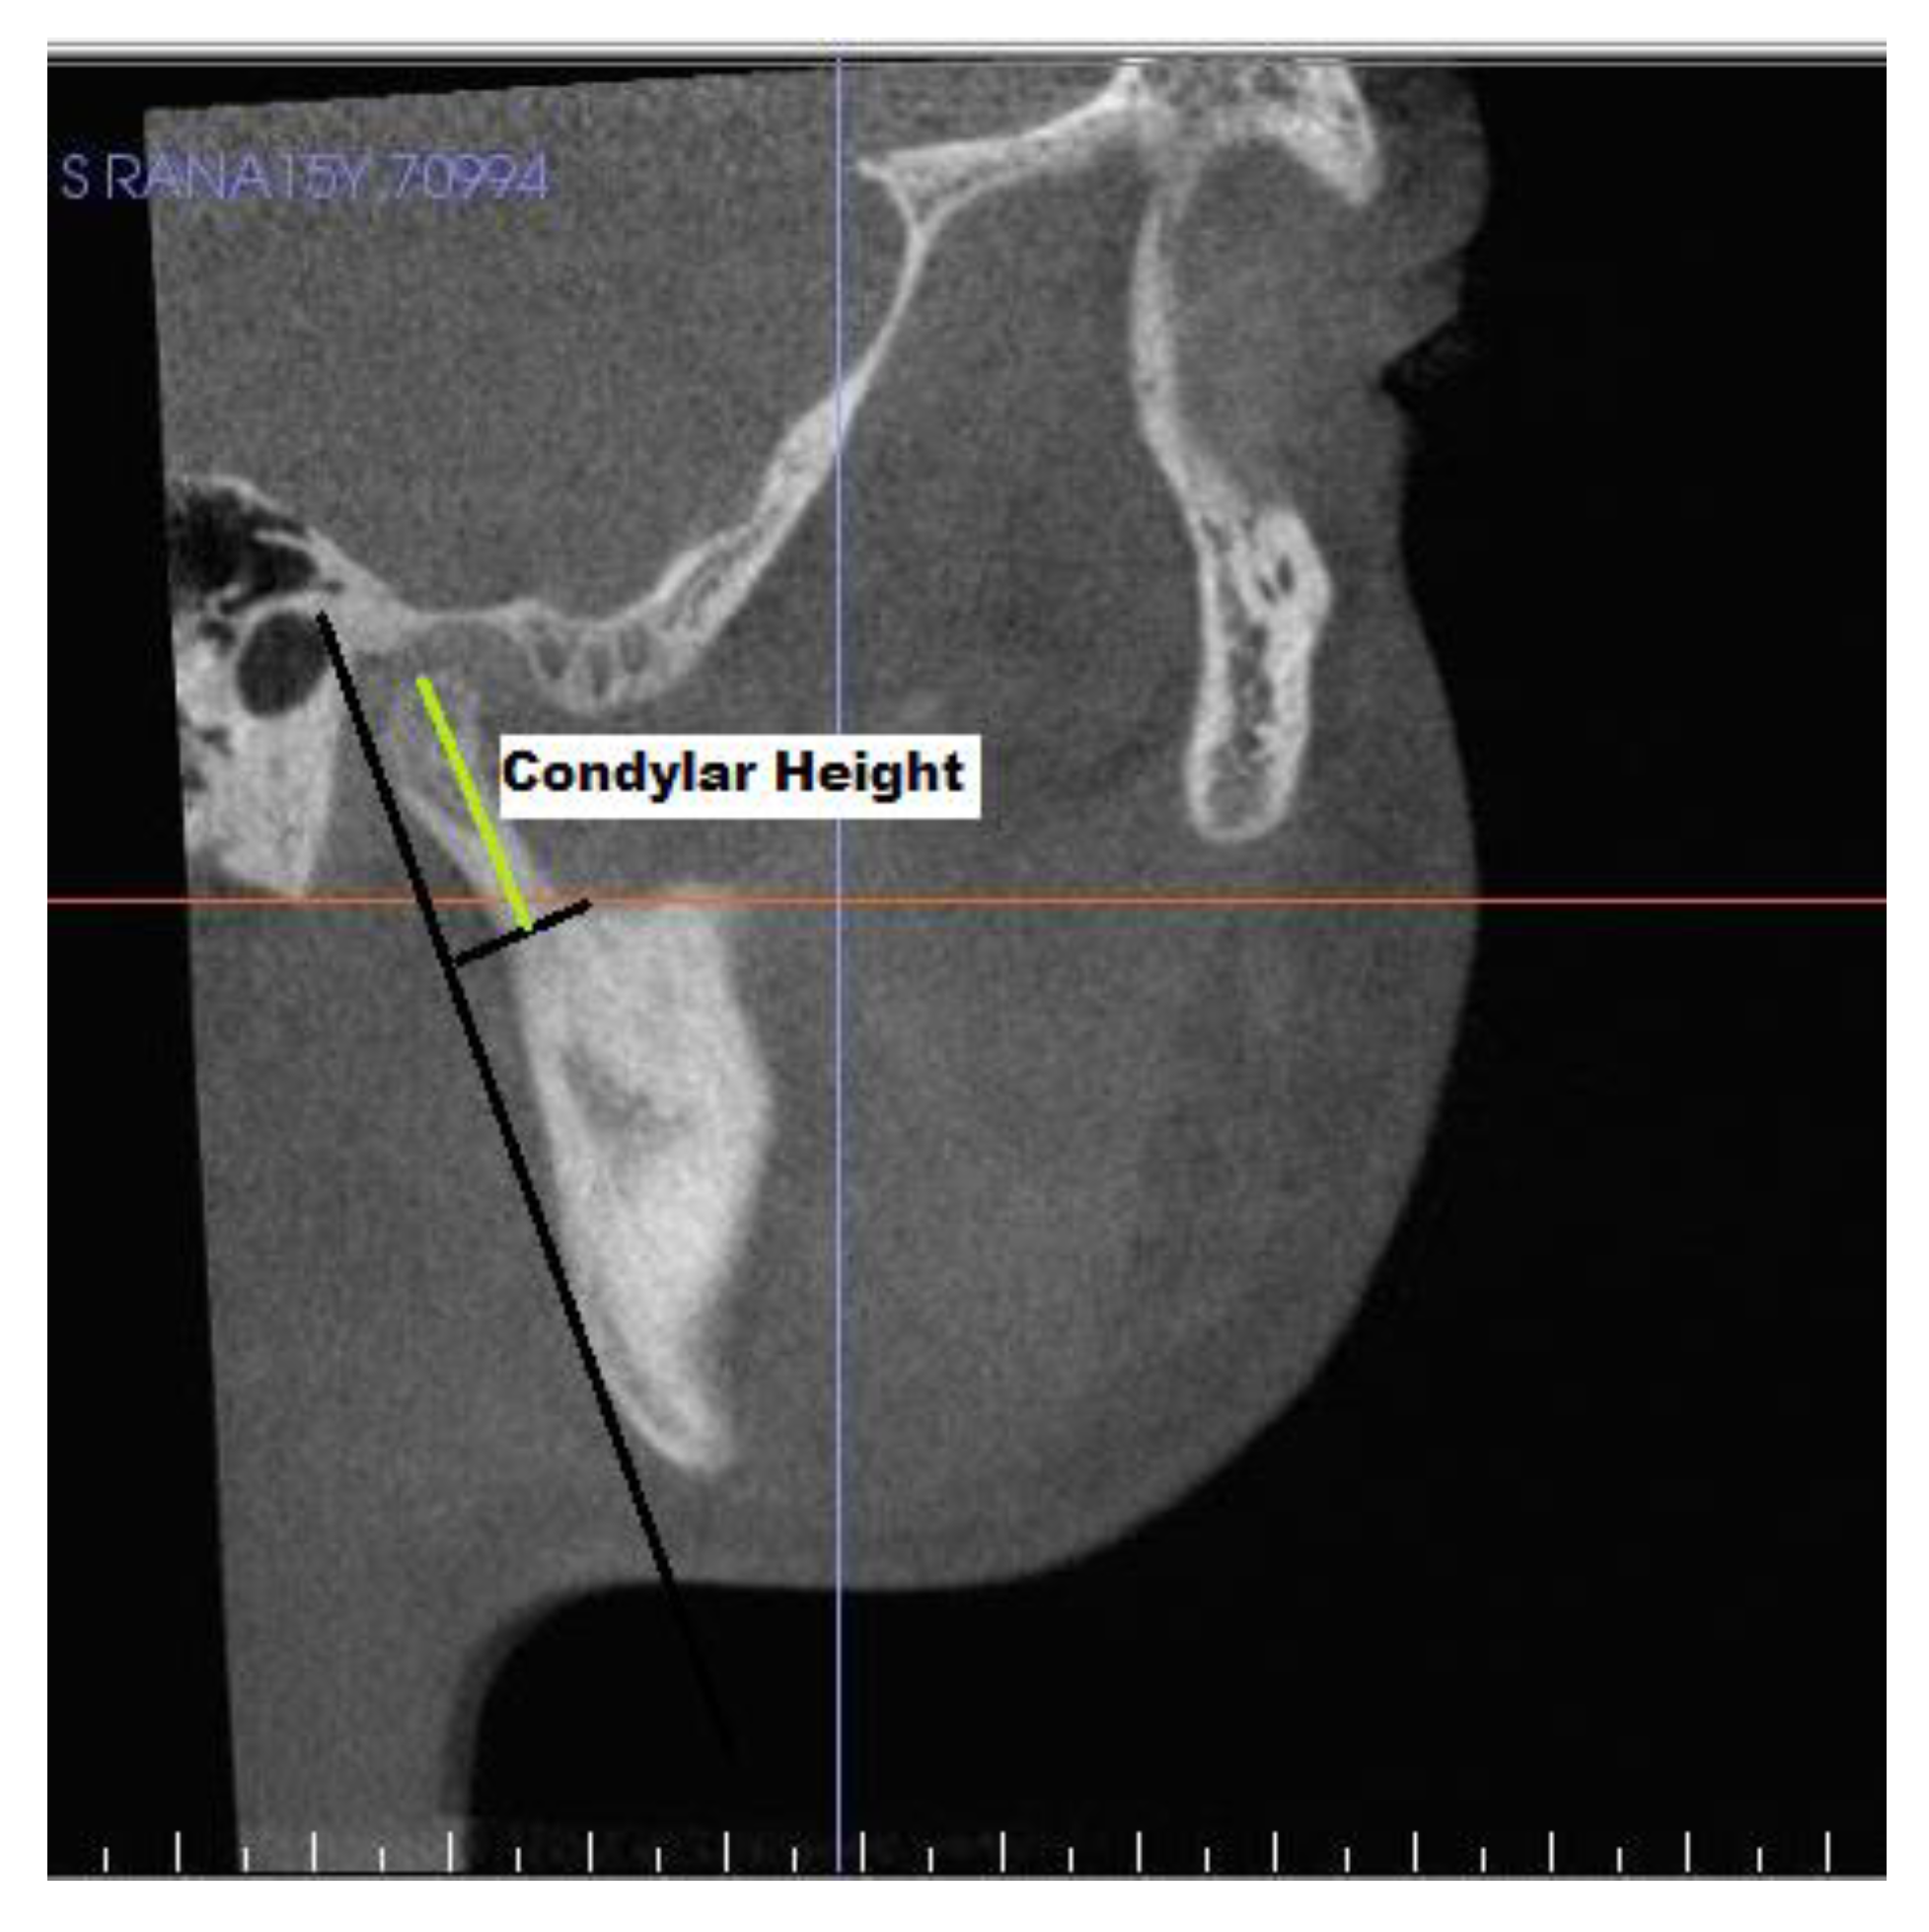

| S. No. | Measurments | Definition |

|---|---|---|

| Condyle | ||

| 11 | Condylar height | Distance from SCo to constructed perpendicular line. |